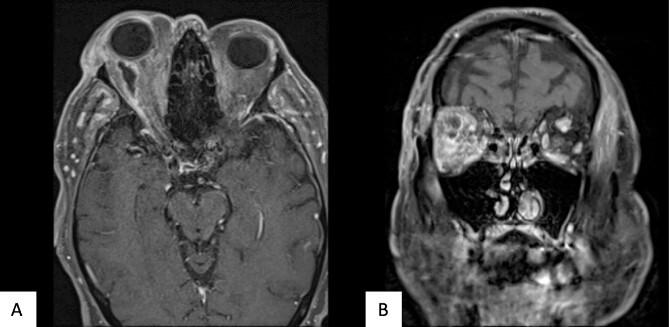

Orbital abscesses are caused by infection within or near the orbit and show obvious signs of pain, proptosis and raised inflammatory markers. Diagnosis is based on clinical features and radiological imaging, and requires early antibiotics and often surgical drainage to save vision. Sub-Tenon's injections of triamcinolone acetonide (TA) have caused localized infections in previous reports, which have responded to therapeutic interventions. Here we report a case where a delayed presentation of an orbital abscess secondary to sub-Tenon's TA for persistent post-operative cystoid macular oedema, without obvious signs of infection, rapidly progressed to cause orbital compartment syndrome. Despite treatment, the patient lost complete vision in the affected eye. This case discusses the rare and unusual cause of abscess formation and a diagnostic dilemma.

眶脓肿由眶内或眶周感染引起,表现出明显的疼痛、眼球突出和炎症指标升高的症状。诊断基于临床特征和影像学检查,需要早期使用抗生素,且常常需要手术引流以挽救视力。既往报道显示,球后注射曲安奈德(TA)可导致局部感染,这些感染对治疗干预有反应。在此,我们报告一例病例,该患者因持续性术后黄斑囊样水肿接受球后TA注射,在无明显感染迹象的情况下,眶脓肿延迟出现,并迅速进展为眶间隔综合征。尽管进行了治疗,患者患眼仍完全失明。本病例讨论了脓肿形成的罕见且不寻常的原因以及诊断难题。